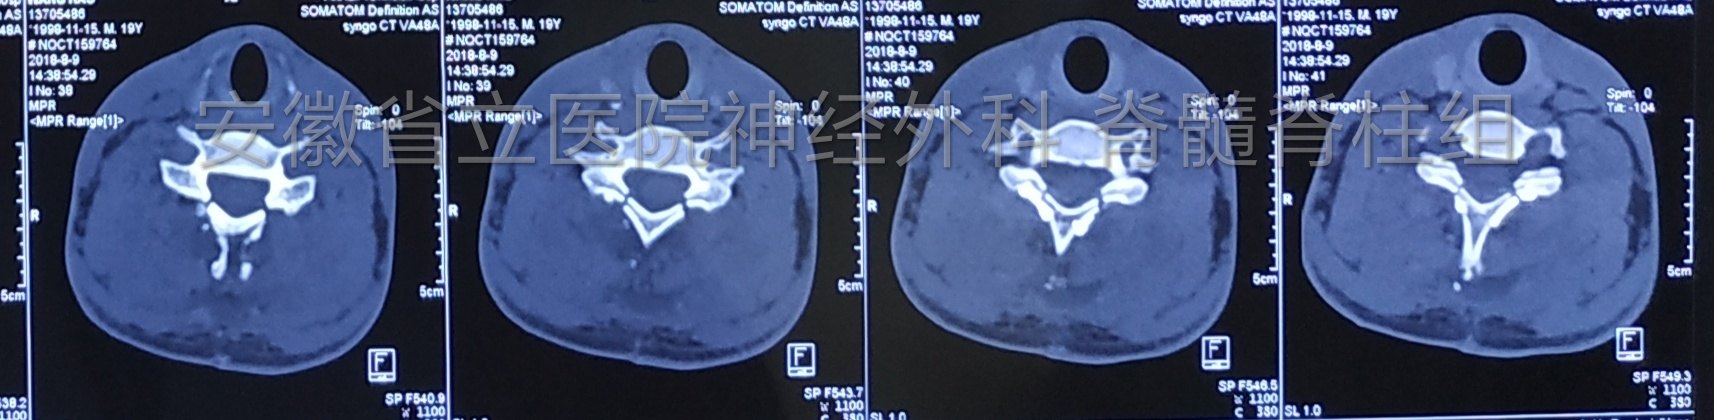

患者17岁,右侧肢体乏力1年入院,查体右侧上肢肌力4级弱,肌肉萎缩。磁共振显示颈椎管占位,完善检查后行手术切除。

肿瘤切除后予以椎板骨质复位,术后复查显示椎管内肿瘤全切除,骨质复位良好,手术部位解剖完整,患者恢复快,脊柱稳定性得以保证。